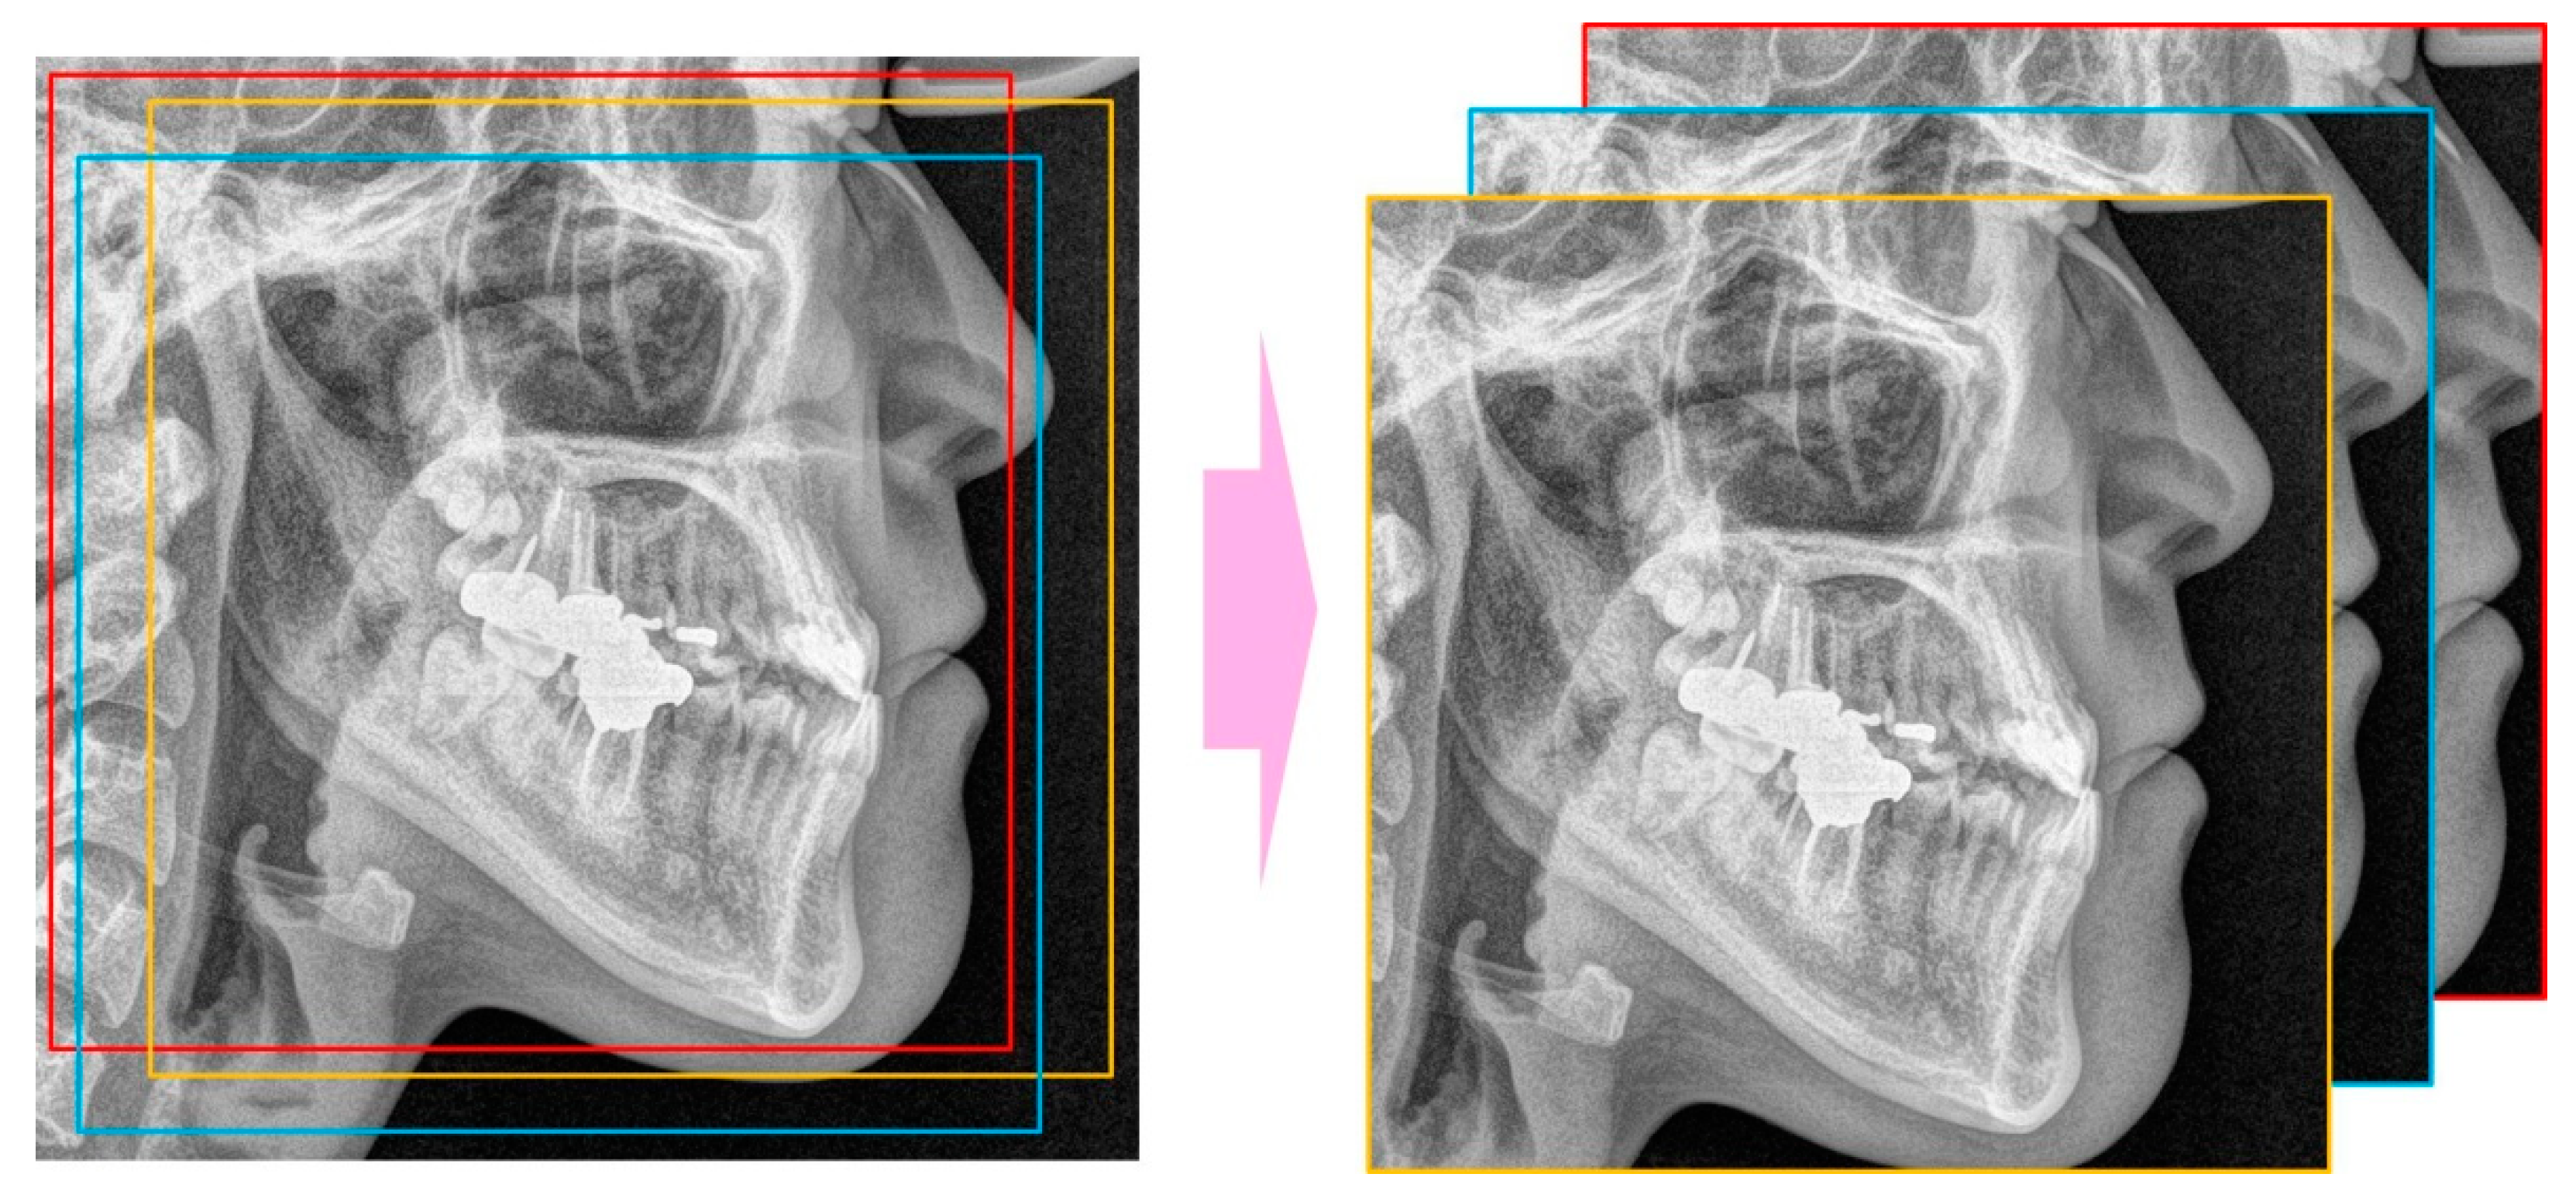

The landmarks of the patients’ cephalometric radiographs were automatically detected with a software program using a gradient boosting algorithm (WebCeph, AssembleCircle, Seoul, Korea). WebCeph has been used for landmark detection in several studies [24,25]. The minimum box, including all the landmarks, was selected with an external margin of 5% and the lower part of the box was selected by square cropping. The image was resized to 256 × 256 pixels.

The CNN models used were ResNet-18, 34, 50, and 101 (Figure 2) [26]. The number was determined by the difference in the depth of the blocks that constitute the model. As ResNet models use an image of 224 × 224 pixels as the default input image, the input image was selected by randomly cropping the 256 × 256 image (Figure 3).

Figure 3.

Random cropping to get 224 × 224 images from 256 × 256 image.